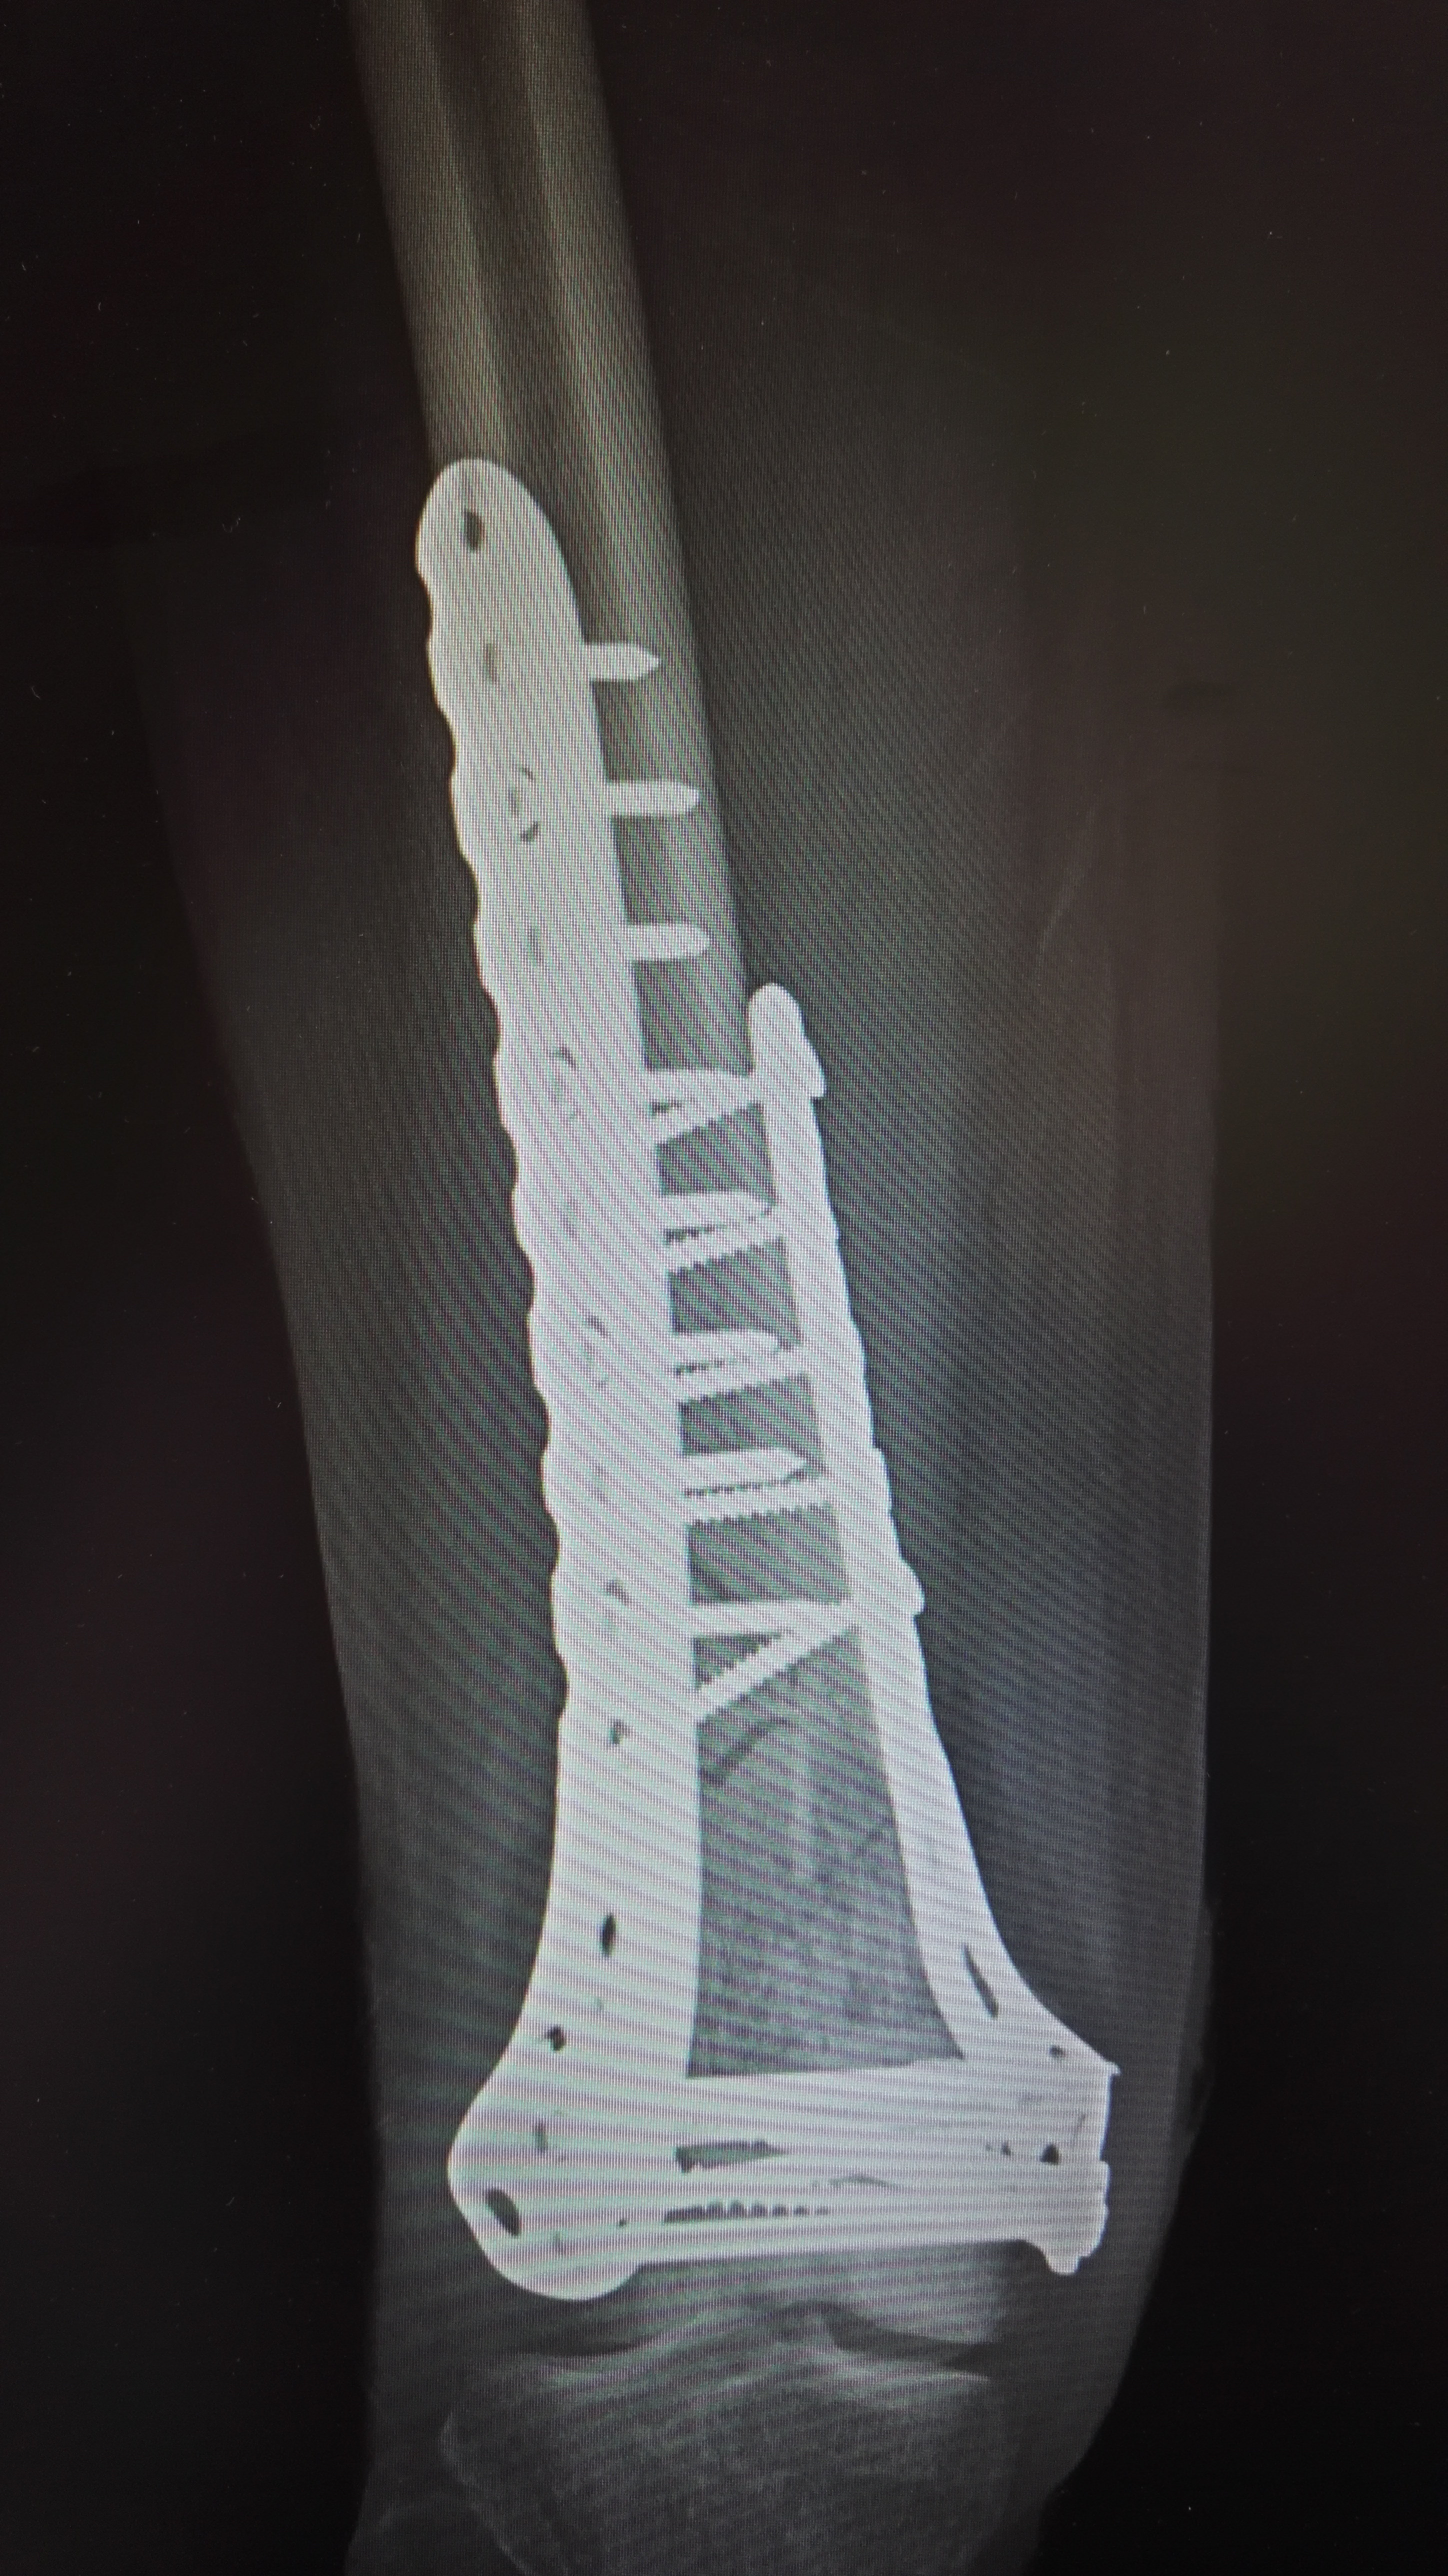

49岁股骨远端骨折微创复位锁定钢板内固定手术一例

股骨远端骨折

下肢股骨远端骨折1例,伴髌骨骨折 - 好大夫在线

股骨远端骨折:考验医生的手术 - 好大夫在线